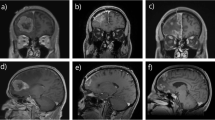

Due to these limitations of postoperative RT, investigators have begun to study the use of neoadjuvant SRS prior to surgical resection. This strategy provides the theoretical benefits of a well-circumscribed target not requiring an additional margin to cover uncertainty in the target volume or areas of intraoperative dissemination. Asher et al. reported the results of 47 patients treated for 51 lesions with preoperative SRS. With a median follow-up time of 12 months, this cohort demonstrated good local control, which was estimated at 98%, 86%, and 72% at 6, 12, and 24 months, with no episodes of radionecrosis reported [56]. Similarly, Prabhu et al. reported on a cohort of 117 patients with 125 lesions treated with preoperative SRS. At 6 months after RT, local control was 75%, regional control of 40%, and the rate of symptomatic radionecrosis was 5% [57]. Based on these results, prospective studies are now underway. A phase II trial in Canada aims to assess the rate of symptomatic radiation toxicity in patients treated with neoadjuvant SRS for up to 10 brain metastases, followed by surgical resection of at least one lesion [58]. NCT03741673 is an ongoing phase III clinical trial comparing preoperative with postoperative SRS with the primary outcome of leptomeningeal disease-free rate [59].

Neoadjuvant SRS for brain metastases is promising, as early results suggest high rates of local control and limited toxicity. Furthermore, completing RT prior to surgery may reduce cost, as RT simulation scans were acceptable as preoperative imaging, and the ability to treat with SRS and surgery in quick succession may help minimize time off systemic therapy. At this time, however, insufficient data exists to justify the treatment of patients with neoadjuvant SRS outside of a clinical trial.